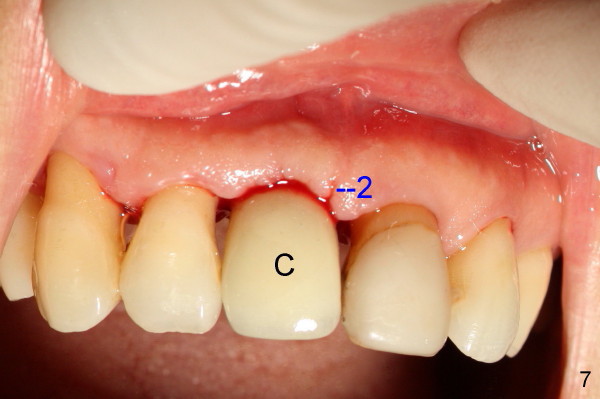

Fig.7 shows the gingiva around the crown (to be cemented) with healing incision #2. Five months after crown cementation, the gingiva looks healthy (Fig.8 blue *, as compared to that of the neighboring tooth, black *). Return to original article